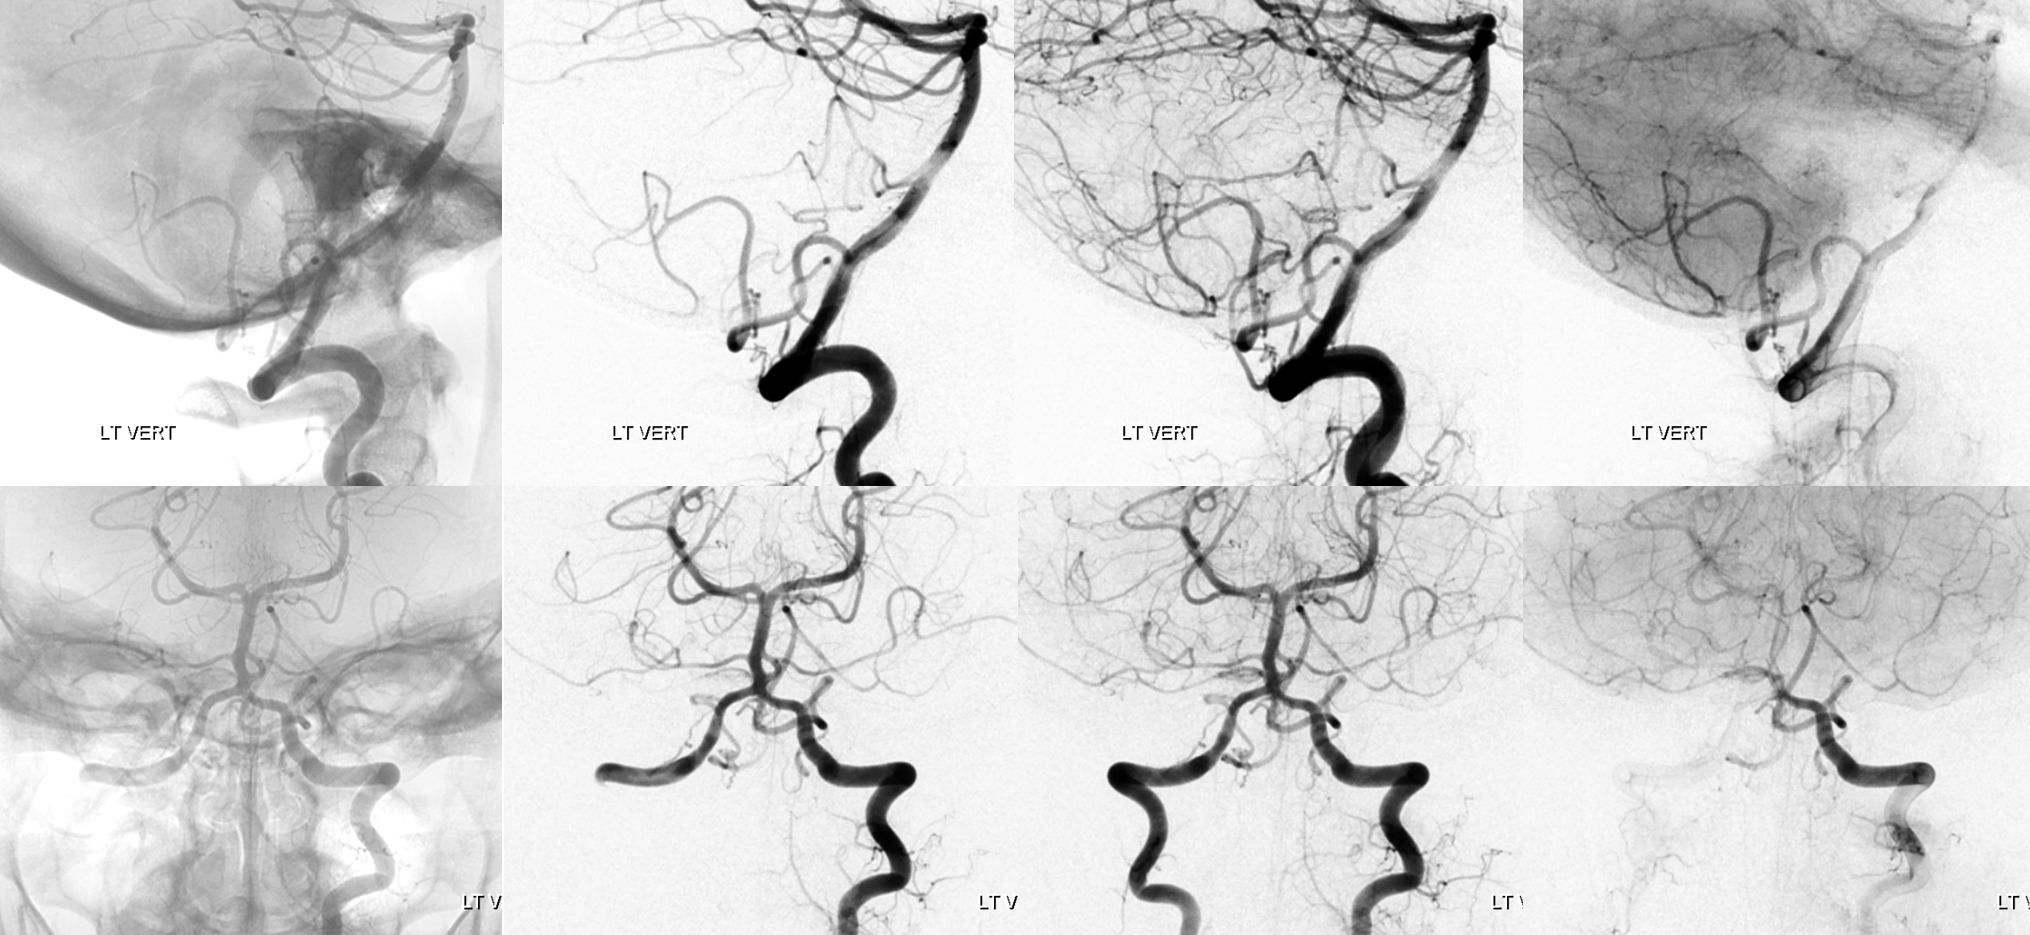

Frontal and lateral angiographic views show occlusion of the left PICA (white arrow) beyond the medullary segment (purple arrows).  Notice clot in the proximal medullary segment, best seen on lateral views.  The is a dominant large PICA with variant bihemispheric supply (pink and black arrows).  Notice truncated appearance where black arrows are corresponding to distal embolic occlusions.  the parenchymal blush is outlined by green arrows.  How is the PICA reconstituted — the most common way it is — via the Lateral Spinal arterial network at C1 (yellow) and proximal intracranial (red) segments (also see examples below).  Notice inferior component of the lateral spinal artery (brown arrow) just below its C1 segment (red arrow).  Brown arrow points to the more typical length of the lateral spinal artery, when seen angiographically. The anterior spinal artery is shown by blue arrow, and is of course anterior to the lateral spinal artery.  This kind of reconstitution has a propensity to form flow-related Lateral Spinal Artery Aneurysms so follow up is needed.